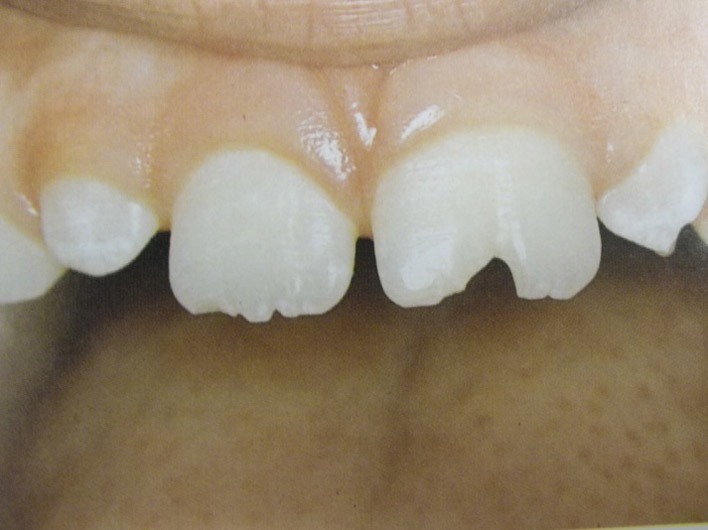

Ανωμαλίες αριθμού, θέσης και σχήματος νεογιλών και μονίμων δοντιών

Υπάρχουν διάφορες καταστάσεις που χρήζουν διάγνωσης και θεραπείας από τον παιδοδοντίατρο. Δείτε τις μία προς μία κάνοντας κλικ στις παρακάτω εικόνες.